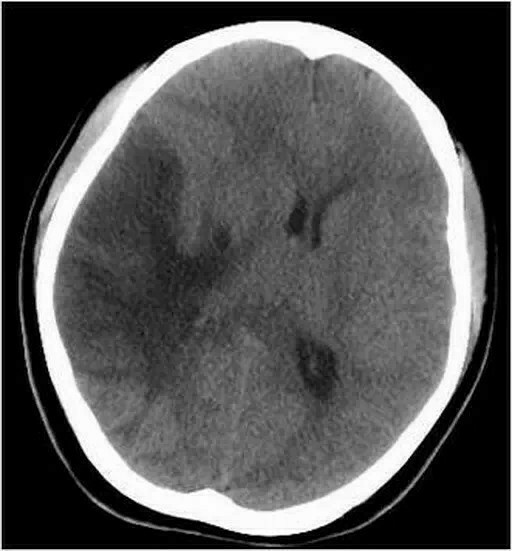

线粒体脑肌病除肌肉症状外,合并中枢神经系统损伤,表现为癫痫发作卒中样发作共济失调认知障碍及视网膜病变等部分亚型如MELAS线粒体脑肌病伴乳酸酸中毒和卒中样发作还可出现耳聋糖尿病等全身症状2 诊断挑战与临床特征该病诊断难度较高,原因包括症状非特异性早期可能仅表现为生长。

乳酸酸中毒卒中样发作伴线粒体脑肌病发病特点青少年发病,卒中样发病症状伴有乳酸升高,有时有脑梗死表现,且梗死灶不符合血管分布区表现墨菲综合征发病特点青少年发病症状肌阵挛发作认知障碍视听障碍病理检查破碎的红纤维总结线粒体脑肌病的症状因疾病分类不同而有所差异,但普遍涉及肌肉神经视听认知等多个系统,且多数在青少年时期发病。